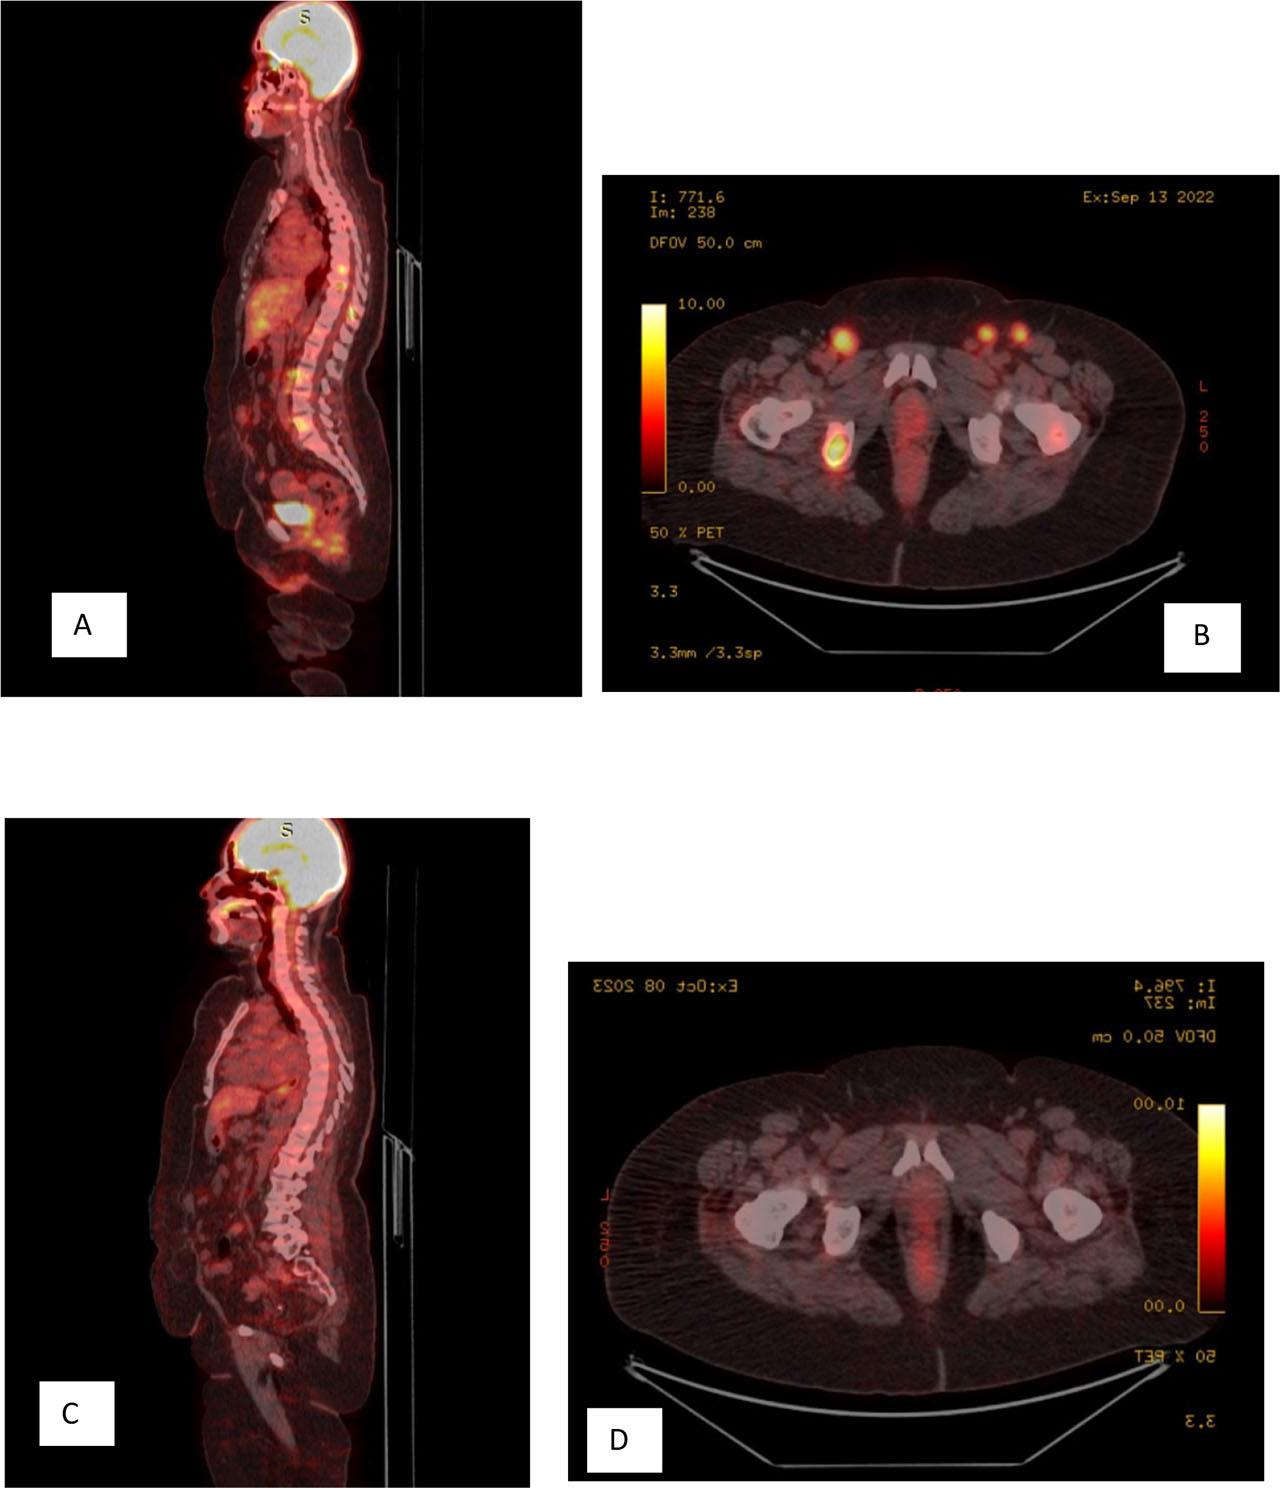

Figure 1:

Figure 2: